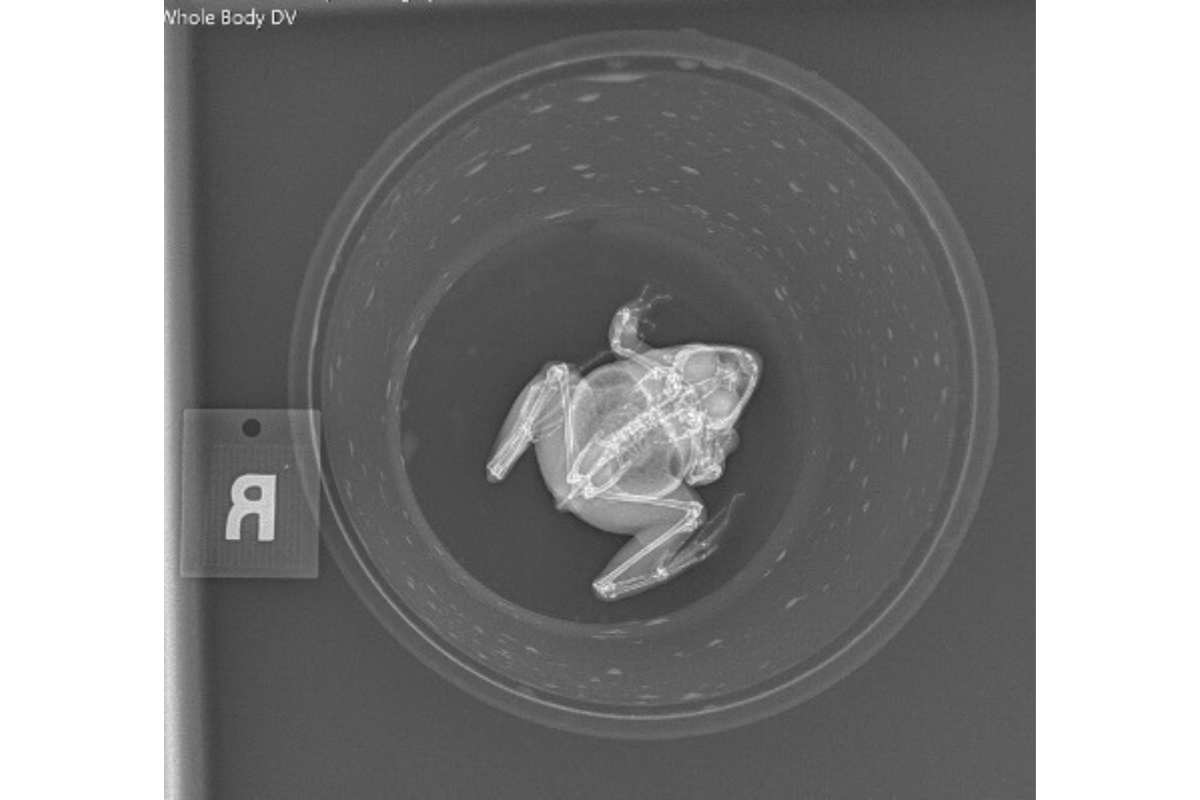

Southern Leopard Frog

On the opposite side, this tiny three-inch frog lives in most of the eastern United States, from New York to Florida. The southern leopard frog calls shallow parts of almost any fresh body of water home.